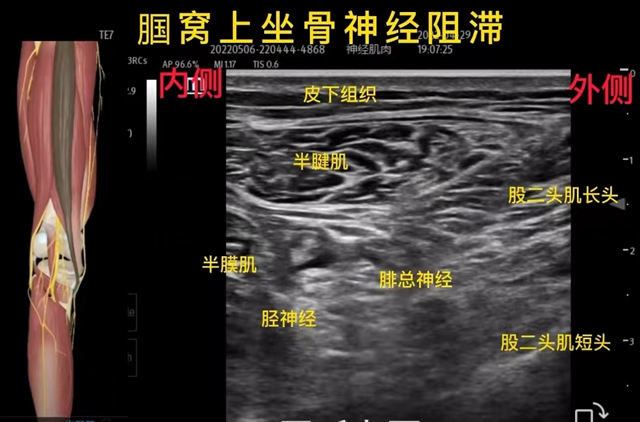

超声引导下神经阻滞治疗

超声引导下神经阻滞治疗可以动态的、实时的对人体的组织进行监测,对神经、肌肉、肌腱、血管、骨骼等有着高清晰的分辨能力。在超声可视化动态监测下,按照神经走行和支配的规律、骨骼功能解剖对原发病灶更准确的进行药物注射。让整个注射过程变成可视化、精准化、更安全,药物使用剂量最小化。